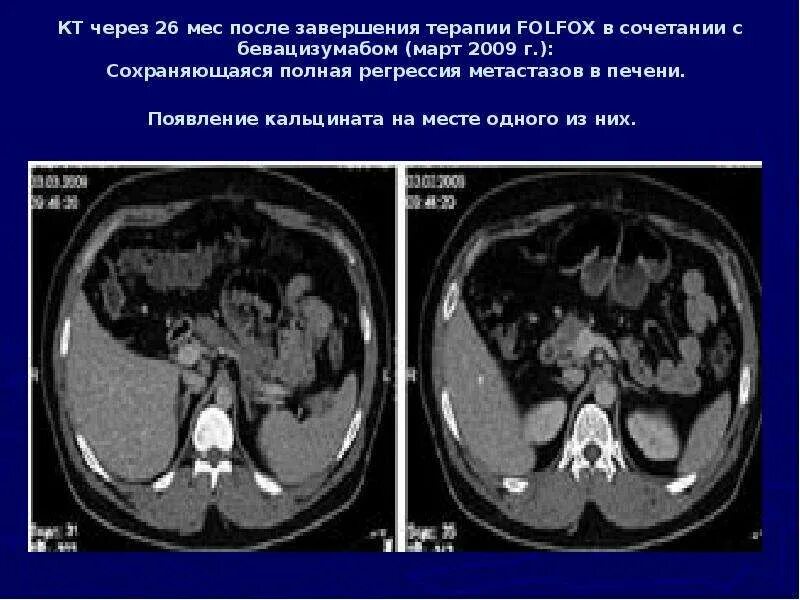

После кт через сколько можно делать мрт